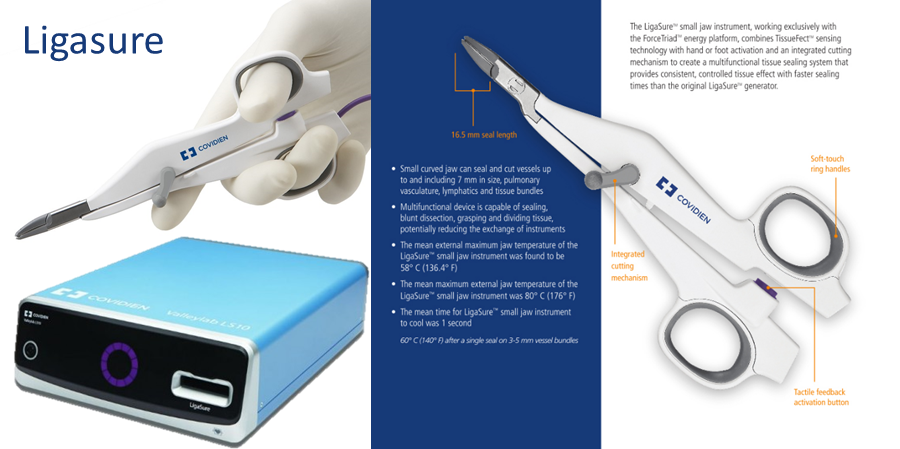

부평프라임동물병원에서는 수술 중 환자의 안전을 위해 출혈을 최소화하는 최신 의료장비 리가슈어를 이용하여 수술을 시행하고 있습니다 리가슈어의료장비는 수술시 절개부위 및 수술부위 출혈이 거의 없어 빠른 시간 내에 혈관을 결찰 또는 분리시켜 수술시간을 획기적으로 단축시킵니다. 그리고 수술 시간의 단축에 의해 마취 시간을 줄일 수 있게 되어, 환자의 회복 시간을 줄일 수 있습니다.